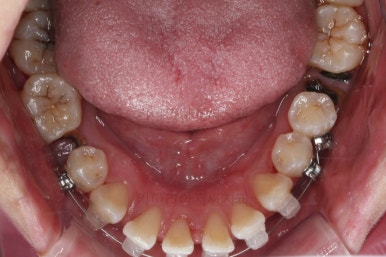

1. 초진

초진 시 입안의 모습입니다.

당장 눈에 띄는 부분은 아래 앞니 사이에 틈새가 있어 치석도 많이 쌓여있는 상황이고요.

윗니-아랫니를 각각 보면 치아가 썩고 부러져 뿌리만 남은 치아가 많이 보입니다.

남은 치아들도 곳곳에 충치가 보이고요.

또 전반적으로 앞니가 앞으로 밀려나와 뻐드러져 있는 모습도 관찰되네요.